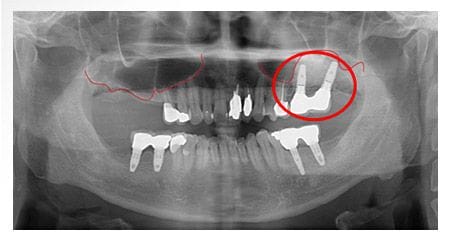

X 光片

術後

標記處補骨並植牙